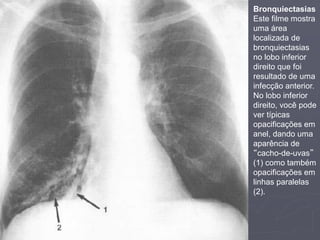

Bronquiectasias

Este filme mostra

uma área

localizada de

no lobo inferior

direito que foi

resultado de uma

infecção anterior.

direito, você pode

ver típicas

opacificações em

anel, dando uma

aparência de

“cacho-de-uvas”

(1) como também

linhas paralelas

(2).